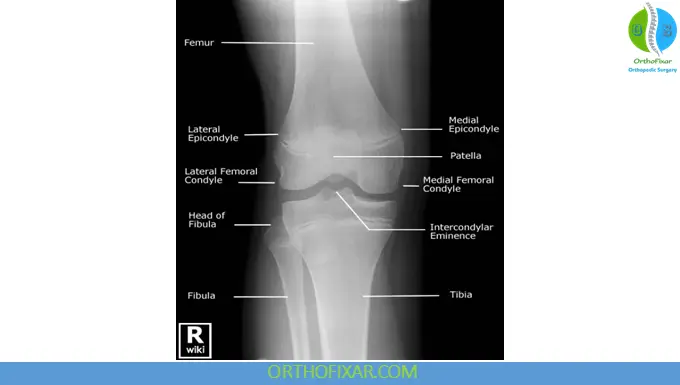

Anteroposterior View

The AP view allows assessment of:

- Fractures (tibial plateau, fibular head, osteochondral lesions)

- Joint space narrowing suggestive of osteoarthritis

- Osteophyte formation (lipping)

- Varus or valgus deformity

- Loose bodies and abnormal calcifications

- Ossification patterns (e.g., Pellegrini–Stieda syndrome)

- Patellar height abnormalities (patella alta or baja)

Weight-bearing AP radiographs in 30° flexion are recommended for suspected degenerative disease. Stress AP views may demonstrate medial or lateral gapping consistent with ligamentous instability.

A healthy knee joint X-ray on AP projection shows symmetric joint spaces, smooth articular margins, and normal alignment